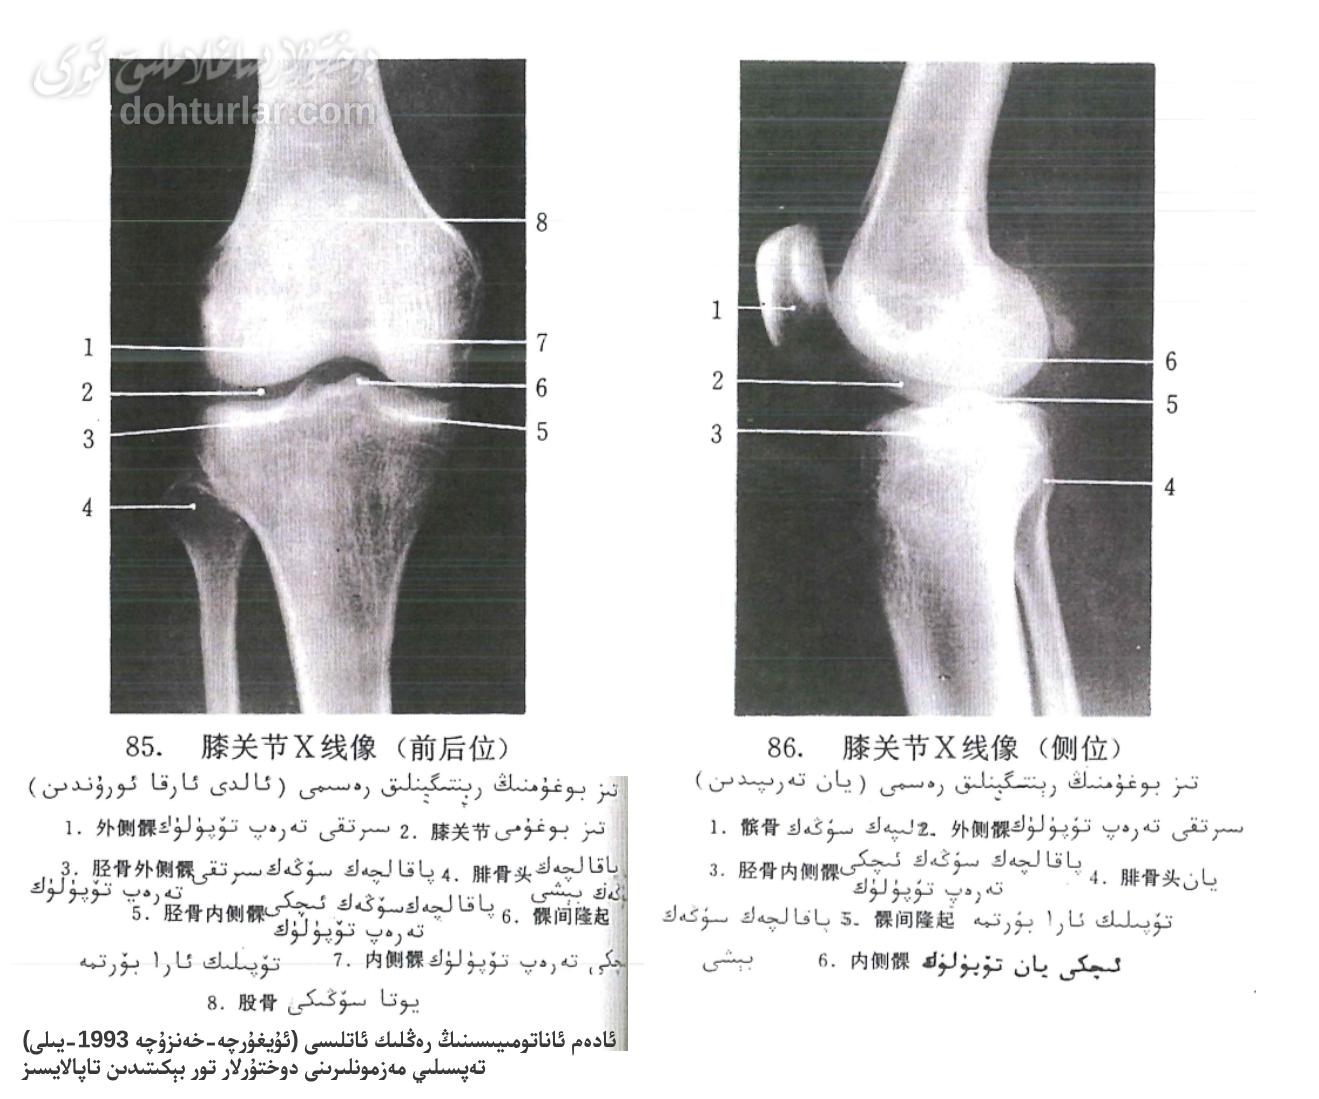

رېنتىگېن تەكشۈرۈشى سۆڭەك كېسەللىكلىرىگە دىئاگنوز قويۇشتىكى ئاساسلىق ۋە كەڭ قوللىنىلىدىغان ۋاسىتىلەرنىڭ بىرى. تىز بوغۇمىنىڭ ئالدى-ئارقا ۋە يان تەرەپ رېنتىگېن سۈرەتلىرى ئارقىلىق، دوختۇرلار سۆڭەكلەرنىڭ تىزىلىشى، بوغۇم بوشلۇقىنىڭ كەڭ-تارلىقى، سۆڭەك ماددىسىنىڭ بۇزۇلۇش-ئۆزگىرىشى ۋە سۇنۇش قاتارلىق ئەھۋاللارنى ئېنىق كۆزىتەلەيدۇ. بۇ ماقالىدە، تىز بوغۇمىنىڭ رېنتىگېنلىك رەسىملىرىدىكى ھەر بىر ئاناتومىيىلىك قۇرۇلمىنى تونۇشتۇرۇش ئارقىلىق، سىزنىڭ تىز بوغۇمىنىڭ فۇنكسىيەسى ۋە كلىنىكىلىق ئەھمىيىتى ھەققىدىكى چۈشەنچىڭىزنى چوڭقۇرلاشتۇرىمىز.

تىز بوغۇمىنىڭ ئاناتومىيىلىك قۇرۇلمىسى

- تىز بوغۇمى (Knee Joint, 膝关节)

ئىنسان بەدىنىدىكى ئەڭ چوڭ ۋە مۇرەككەپ بوغۇم بولۇش سۈپىتى بىلەن، ئۇ ئاساسلىقى يوتا سۆڭىكىنىڭ تۆۋەنكى ئۇچى، پاقالچاق سۆڭىكىنىڭ يۇقىرىقى ئۇچى ۋە لىپەك سۆڭىكىدىن تەشكىل تاپىدۇ. تىز بوغۇمى پۇتنىڭ ئېگىلىش ۋە يېزىلىش ھەرىكىتىنى ئىشقا ئاشۇرۇپلا قالماي، بەدەن ئېغىرلىقىنى كۆتۈرۈش ۋە ھەرىكەت جەريانىدىكى زەربىنى ئازايتىشتىمۇ ھالقىلىق رول ئوينايدۇ. ئۇنىڭ تۇراقچانلىقى ۋە جانلىقلىقى ئەتراپىدىكى مۇسكۇل، كىرپىك ۋە بوغۇم سومكىسى قاتارلىق يۇمشاق توقۇلمىلار تەرىپىدىن قوغدىلىدۇ. تىز بوغۇمىنىڭ ساغلاملىقى كۈندىلىك پائالىيەتلەرنىڭ راۋان بولۇشى ئۈچۈن ئىنتايىن مۇھىم. - يوتا سۆڭىكى (Femur, 股骨)

يوتا سۆڭىكى بەدەندىكى ئەڭ ئۇزۇن ۋە ئەڭ پۇختا سۆڭەك بولۇپ، تىز بوغۇمىنىڭ يۇقىرىقى قىسمىنى تەشكىل قىلىدۇ. ئۇنىڭ تۆۋەنكى ئۇچىدا ئىچكى ۋە سىرتقى تۆپۈلۈكلەر بولۇپ، پاقالچاق سۆڭىكى بىلەن بوغۇم ھاسىل قىلىدۇ. - سىرتقى تەرەپ تۆپۈلۈك (Lateral Femoral Condyle, 外侧髁)

بۇ يوتا سۆڭىكىنىڭ تۆۋەنكى ئۇچىدىكى سىرتقا جايلاشقان بوغۇم يۈزى بولۇپ، پاقالچاق سۆڭىكىنىڭ سىرتقى تەرەپ تۆپۈلۈكى بىلەن ئۇلىنىدۇ. ئۇ تىز بوغۇمىنىڭ تۇراقلىقلىقىنى ساقلاش ۋە ھەرىكەتنى راۋانلاشتۇرۇشتا مۇھىم رول ئوينايدۇ. - ئىچكى تەرەپ تۆپۈلۈك (Medial Femoral Condyle, 内侧髁)

يوتا سۆڭىكىنىڭ تۆۋەنكى ئۇچىدىكى ئىچكى تەرەپكە جايلاشقان بوغۇم يۈزى بولۇپ، پاقالچاق سۆڭىكىنىڭ ئىچكى تەرەپ تۆپۈلۈكى بىلەن ئۇلىنىپ، بوغۇمنىڭ ئاساسلىق ئېغىرلىق كۆتۈرۈش قىسمىنى ھاسىل قىلىدۇ. بۇ قۇرۇلما تىزنىڭ نورمال ئېگىلىش ۋە يېزىلىش ھەرىكىتىگە كاپالەتلىك قىلىدۇ. - پاقالچەك سۆڭەك سىرتقى تەرەپ تۆپۈلۈك (Lateral Tibial Condyle, 胫骨外侧髁)

پاقالچاق سۆڭىكىنىڭ يۇقىرىقى ئۇچىدىكى سىرتقى بوغۇم يۈزى بولۇپ، يوتا سۆڭىكىنىڭ سىرتقى تەرەپ تۆپۈلۈكى بىلەن ماسلىشىپ بوغۇم ھاسىل قىلىدۇ. بۇ رايون تىز بوغۇمىنىڭ ھەرىكەت دائىرىسىنى ۋە تۇراقچانلىقىنى بەلگىلەيدىغان مۇھىم قىسىم. - پاقالچەك سۆڭەك ئىچكى تەرەپ تۆپۈلۈك (Medial Tibial Condyle, 胫骨内侧髁)

پاقالچاق سۆڭىكىنىڭ يۇقىرىقى ئۇچىدىكى ئىچكى بوغۇم يۈزى بولۇپ، يوتا سۆڭىكىنىڭ ئىچكى تەرەپ تۆپۈلۈكى بىلەن ئۇلىنىدۇ. ئۇ تىز بوغۇمىنىڭ ئېغىرلىق كۆتۈرۈش ئىقتىدارىنى ئۈستىگە ئالغان ئاساسلىق قۇرۇلمىلارنىڭ بىرى. - تۆپۈلۈك ئارا ھۈررىكى (Intercondylar Eminence, 髁间隆起)

بۇ قۇرۇلما پاقالچاق سۆڭىكىنىڭ ئىچكى ۋە سىرتقى تۆپۈلۈكلىرى ئارىسىغا جايلاشقان سۆڭەكلىك دۆڭچە بولۇپ، ئالدى ۋە ئارقا كىرىشسىمان كىرپىكلەرنىڭ چاپلىنىش نۇقتىسى ھېسابلىنىدۇ. ئۇ تىز بوغۇمىنىڭ ئالدى-كەينى يۆنىلىشىدىكى تۇراقلىقلىقىنى ساقلاشتا ھالقىلىق رول ئوينايدۇ. - يان پاقالچەك سۆڭەك بېشى (Head of Fibula, 腓骨头)

يان پاقالچاق سۆڭىكى پۇتنىڭ سىرتقى تەرىپىگە جايلاشقان نېپىز سۆڭەك بولۇپ، ئۇنىڭ يۇقىرىقى ئۇچى «باش قىسمى» دەپ ئاتىلىدۇ. ئۇ تىز بوغۇمىنىڭ بىۋاسىتە تەركىبىي قىسمى بولمىسىمۇ، سىرتقى يان كىرپىك ۋە بەزى مۇسكۇللارنىڭ چاپلىنىش نۇقتىسى بولۇش سۈپىتى بىلەن، تىزنىڭ يان تەرەپ تۇراقلىقلىقىغا ياردەم بېرىدۇ. - لىپەك سۆڭەك (Patella, 髌骨)

ئادەتتە «تىز كۆزى» دەپ ئاتىلىدىغان بۇ سۆڭەك، تىز بوغۇمىنىڭ ئالدى تەرىپىگە جايلاشقان ئەڭ چوڭ ئۇرۇقچىسىمان سۆڭەك. ئۇ تۆت باشلىق مۇسكۇلنىڭ كۈچىنى پاقالچاق سۆڭىكىگە ئۈنۈملۈك يەتكۈزۈپ، تىزنى قوغداش ۋە ھەرىكەت ئۈنۈمىنى ئاشۇرۇش رولىنى ئوينايدۇ.